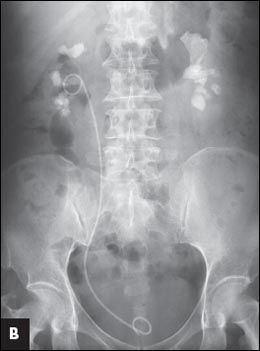

). Treatment results are shown after the first percutaneous nephrolithotomy (PCNL) and removal of the ureteral stone (

B

) and after the second PCNL (

The patient underwent transurethral incision of the right ureterocele and ureteroscopic removal of the ureteral stone. Simultaneous right percutaneous nephrolithotomy (PCNL) was performed, and a ureteral stent was inserted at the end of the procedure (Figure 1B). Second stage right PCNL for the residual stones was performed 2 weeks later, and all the stones were cleared (Figure 1C). Left PCNL was also performed with clearance of all the residual stones (Figure 1D). Stone analysis revealed that the calculi were composed of 76% magnesium ammonium phosphate (struvite) and 24% calcium carbonate apatite.